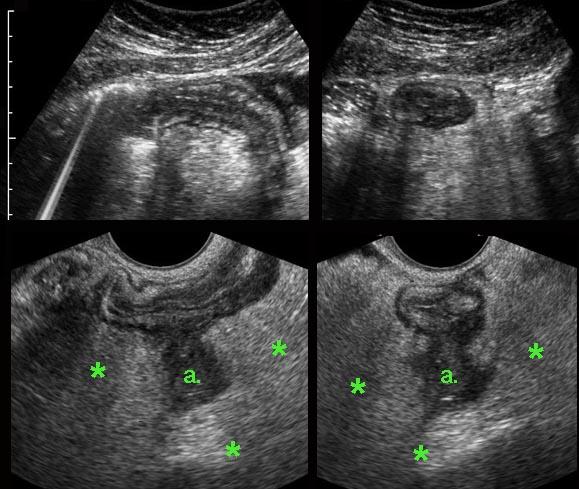

DIE tại trực tràng

Các hình ảnh thuộc về một bệnh nhân DIE với hình thái tử cung và buồng trứng bình thường.

DIE có các đặc điểm TVUS điển hình, gần như đặc trưng bệnh lý.

Mặc dù rõ ràng là một bệnh lý phụ khoa, nhưng không hiếm trường hợp bị các bác sĩ phụ khoa bỏ sót trong quá trình thực hiện TVUS.

Lý do là phần lớn bệnh nhân DIE (*) không có các nang lạc nội mạc tử cung điển hình và, như ở bệnh nhân này, có tử cung và buồng trứng bình thường (buồng trứng trái và buồng trứng phải). Hơn nữa, chẩn đoán TVUS của DIE đòi hỏi kiến thức chuyên sâu về hình ảnh siêu âm của ruột và bàng quang bình thường cũng như bệnh lý, kiến thức này có thể còn thiếu ở các bác sĩ phụ khoa.

Các ổ lạc nội mạc tử cung trên bề mặt ngoài của đại tràng ở bốn bệnh nhân khác nhau.

Các ổ lạc nội mạc tử cung (*) trong túi cùng Douglas là các khối đặc, giảm âm, kém mạch máu, khu trú không đối xứng, liên tục với lớp cơ giảm âm phía ngoài của đại tràng.

Lớp dưới niêm mạc tăng âm phía trên và niêm mạc đại tràng thường còn nguyên vẹn. Điều này cũng giải thích tại sao máu trong phân khá hiếm gặp trong DIE.

Bờ ngoài của các khối giảm âm này thường dính chặt vào tử cung và/hoặc cổ tử cung. Thường có thể thấy hình ảnh tua gai hoặc “kéo căng” ở các bờ ngoài.

Hình ảnh TVUS của DIE kèm theo bệnh phẩm phẫu thuật.

Ở bệnh nhân này, lớp dưới niêm mạc tăng âm của thành đại tràng sigma mặt trước rõ ràng phủ lên trên ổ lạc nội mạc tử cung lớn (*). Lưu ý thành đại tràng sigma mặt sau hoàn toàn bình thường.

Bệnh phẩm cắt bỏ cho thấy lớp (dưới) niêm mạc (các mũi tên) còn nguyên vẹn và phủ lên trên DIE (*). Đúng như dự đoán, bệnh nhân này cũng không có tiền sử chảy máu trực tràng.